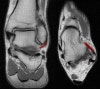

1. Anterior Talofibular ligament

Coronal (left) and axial (right) T1W images assessing the normal normal anterior talofibular ligament.